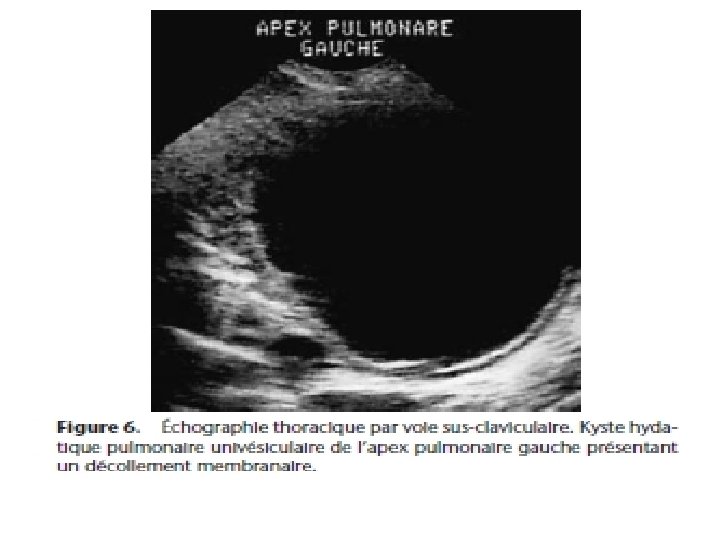

2) Kyste malade ou kyste flétri. Stade clinique= expectoration hémoptoïque, peu abondante; et RX= opacité ronde, surmontée à son pôle supérieur du classique ménisque gazeux 3) Vomique: stade exclusivement clinique; rejet brutal de la vomique (parfois dramatique s’accompagnant de choc anaphylactique) ou vomique fractionnée

Imagerie médicale